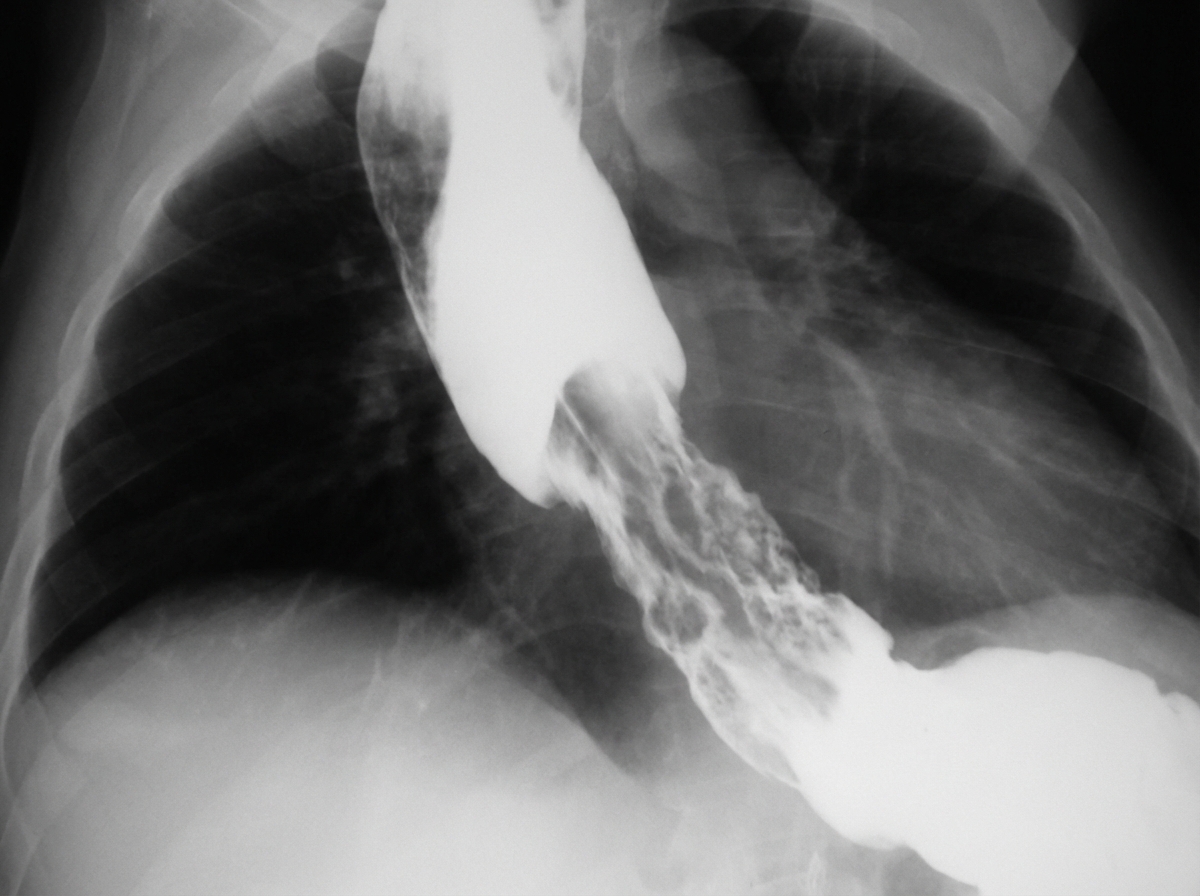

A 64-year-old man develops increasing dysphagia over many months. A barium swallow is performed. What is the most likely cause of his clinical presentation?

Explanation: ***Carcinoma of the esophagus*** - Progressive dysphagia in a **64-year-old male** with **irregular narrowing** and **shouldering/apple-core appearance** on barium swallow is characteristic of **esophageal carcinoma**. - The **rat-tail sign** and abrupt transition from normal to narrowed esophagus strongly suggests malignant stricture rather than benign causes. *Achalasia* - Typically presents with **bird-beak appearance** on barium swallow showing smooth, symmetrical tapering at the gastroesophageal junction. - Characterized by **failure of lower esophageal sphincter relaxation** with associated **esophageal dilatation** proximal to the obstruction. *Sliding hiatal hernia* - Shows **gastroesophageal junction displacement** above the diaphragm with a **bell-shaped** or **tulip-shaped** appearance on barium swallow. - Usually causes **gastroesophageal reflux symptoms** rather than progressive mechanical dysphagia seen in this case. *Paraoesophageal hernia* - Demonstrates **herniation of gastric fundus** alongside the esophagus while the **gastroesophageal junction remains below the diaphragm**. - Typically presents with **chest pain** and **early satiety** rather than progressive dysphagia, and shows characteristic **upside-down stomach** appearance.